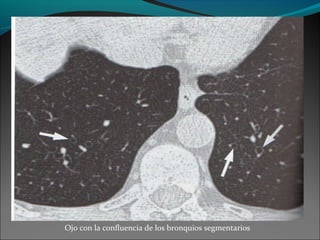

Ojo con la confluencia de los bronquios segmentarios

Ojo con laconfluencia de los bronquios segmentarios